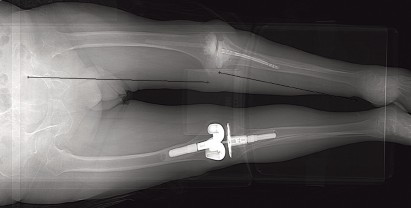

Introduction Minimally invasive surgery (MIS) for knee arthroplasty began with work on unicondylar knee repla…